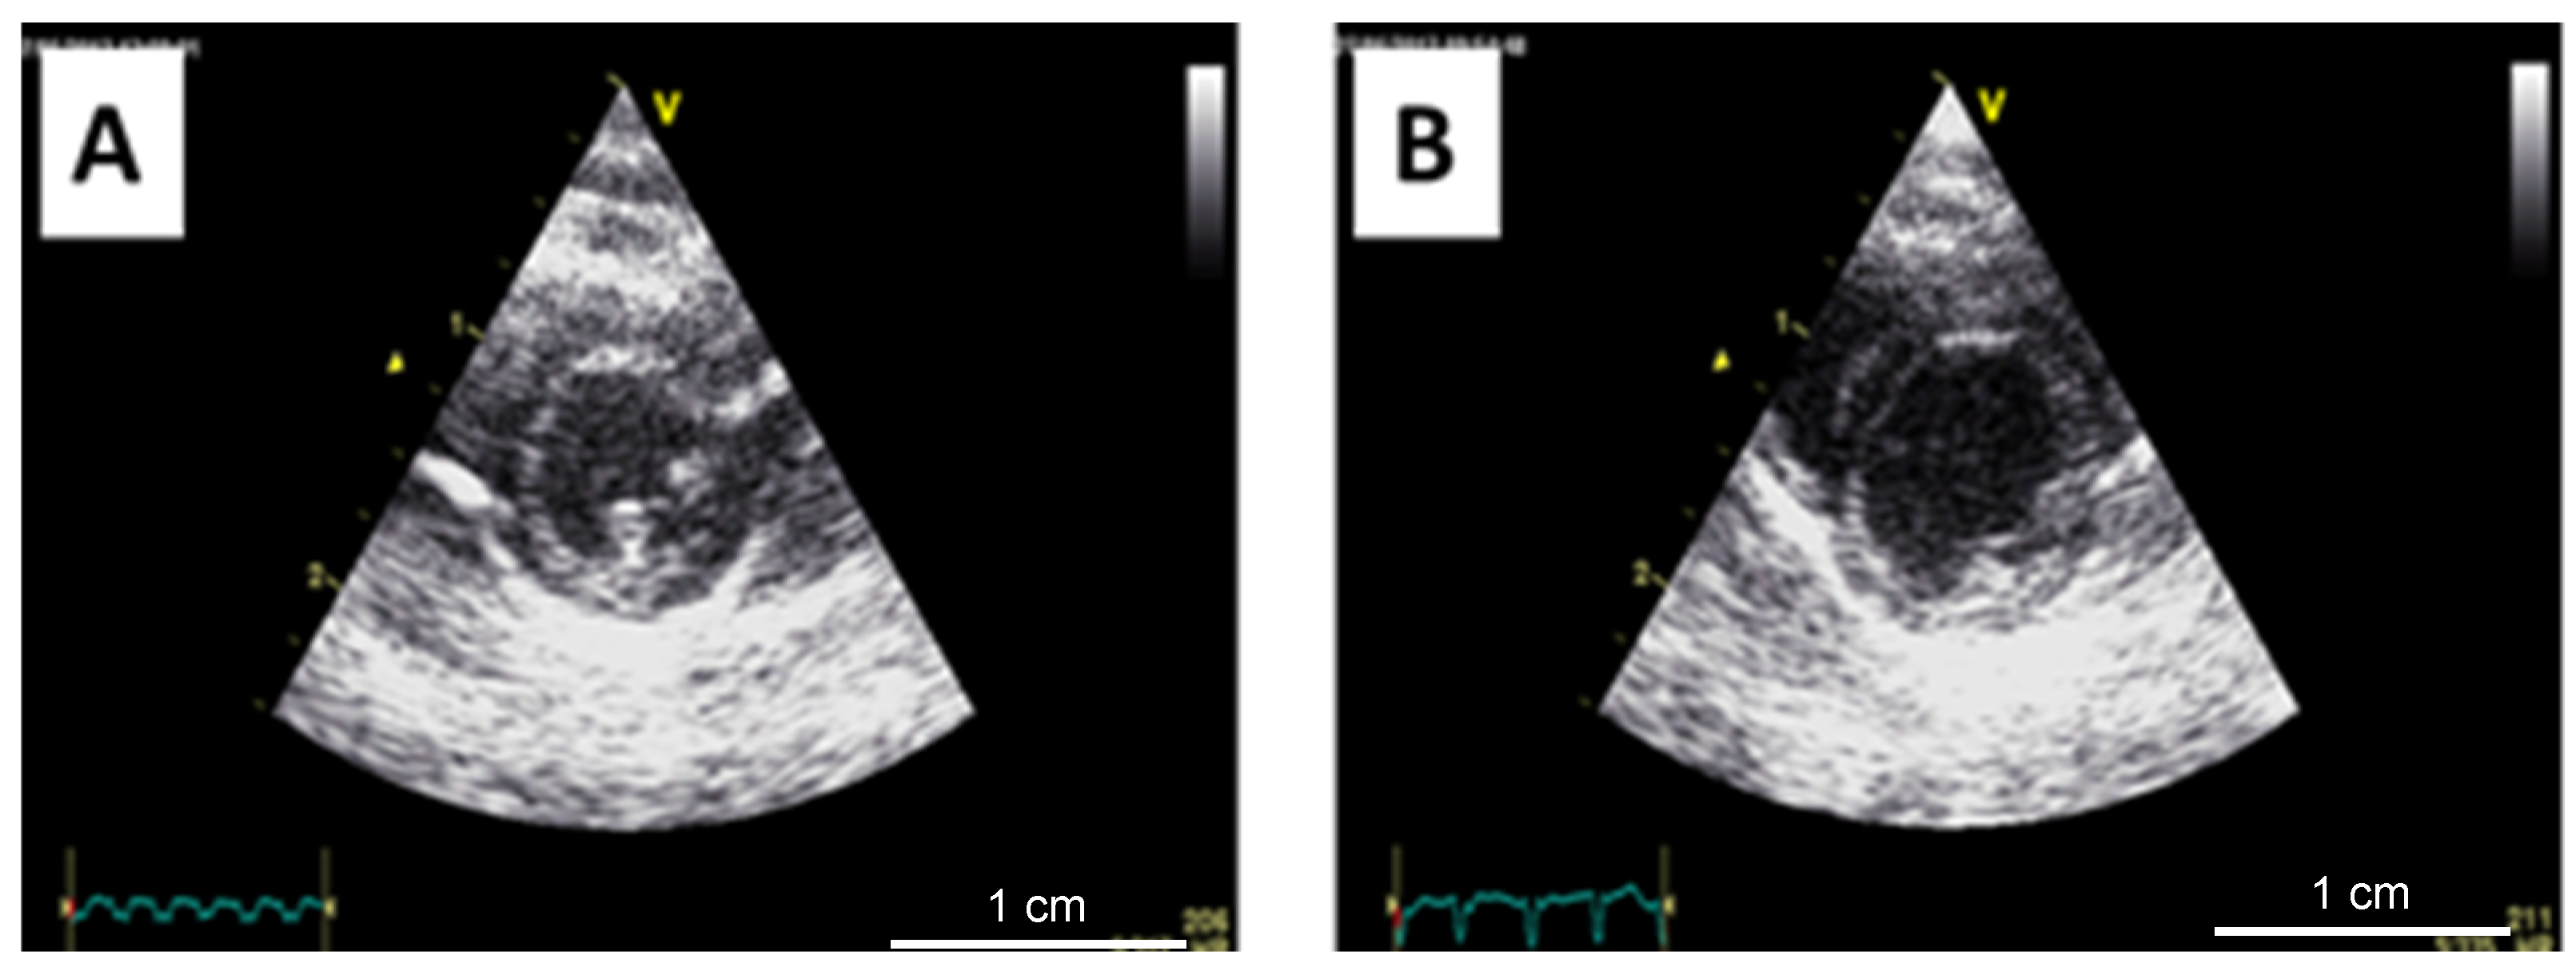

2.2. Echocardiography

3.2. Echocardiographic Parameters in the Two Models